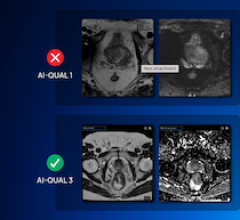

A new study published in JCO Clinical Cancer Informatics tackles a critical challenge in cancer diagnostics: ensuring ...

June 26, 2025 – Quibim, a global provider of quantitative medical imaging solutions, has launched AI-QUAL, a new feature ...